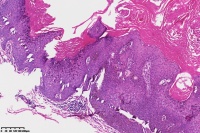

脂溢性角化症伴皮角?

女

年龄

49岁

手臂皮肤组织

图4

脂溢性角化病